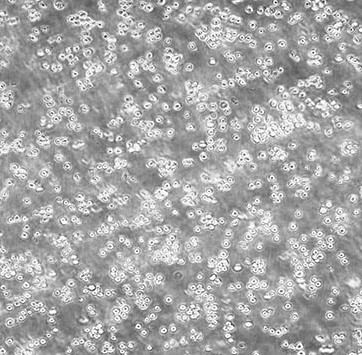

MOLT-4